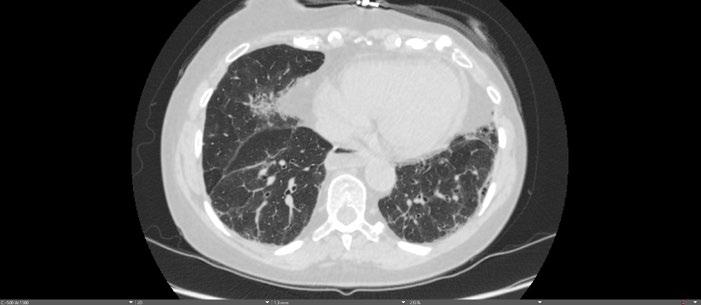

In contrast to acute complications, chronic complications are generally more unique to the Caesarean section itself, and are not typically seen with other surgical procedures, with the exception of incisional hernia. Caesarean scar niche was identified as an important cause of pain and irregular bleeding (Figure 1).

C-section: Caesarean section; US: ultrasound.

A B C D E F G H J K L M I Abstract ● ECR 2024 Creative Commons Attribution-Non Commercial 4.0 ● April 2024 ● Radiology 23

Figure 1: Caesarean scar niche.